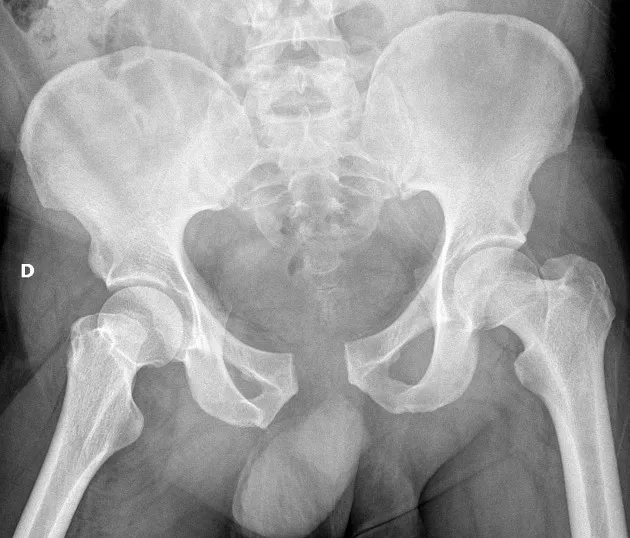

3.Beeldvorming: Bij vermoeden van een bekkenfractuur wordt direct beeldonderzoek ingezet. Een röntgenfoto van het bekken kan grote breuken aantonen. Vaak is aanvullend een CT-scan nodig om de breukdetails en verplaatsing goed in kaart te brengen. Een CT-scan toont welke delen van de bekkenring gebroken zijn en of de heupkom (acetabulum) betrokken is. Eventueel wordt, bij verdenking op bloedingen, ook een echografie (FAST-scan) of CT van de buik gedaan om inwendig bloedverlies te beoordelen. MRI is zelden nodig in de acute fase, behalve bij twijfel over kleine breukjes die op de CT niet duidelijk zijn.

Een bekkenbreuk is een ernstig letsel van de bekkenring, vaak veroorzaakt door een zwaar ongeval of bij ouderen door een val bij osteoporose. Typische symptomen zijn hevige pijn en onmogelijkheid om nog te lopen. De diagnose wordt gesteld met beeldvorming (RX en CT) en de behandeling varieert van pijnstilling en rust tot operatief vastzetten, afhankelijk van de stabiliteit van de bekkenfractuur. Vroege herkenning en aangepaste behandeling zijn cruciaal, want bij instabiele bekkenfracturen kan inwendig bloedverlies levensbedreigend zijn. Met de juiste aanpak – eventueel inclusief specialistische chirurgie – kan een bekkenbreuk goed herstellen. De revalidatie vergt geduld en inzet: men start voorzichtig met mobilisatie om complicaties te voorkomen. Uiteindelijk kunnen veel patiënten hun gewone dagelijkse activiteiten hervatten. Bij eenvoudige bekkenbreuken is volledig herstel haalbaar, terwijl complexere breuken soms restklachten geven.